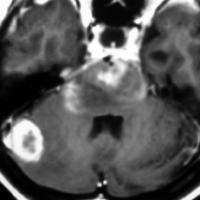

4歳の時に低線量頭蓋照射を受けていますが,医療関係の仕事について自立していた33歳の女性です。仕事中に記憶が飛ぶという症状がでて,周囲からおかしいと言われて受診しました。右の扁桃体のところ(左側のMRI)に海綿状血管腫ができていて,側頭葉てんかん(欠伸発作)を生じていました。バルプロ酸の投与で発作は止まって職場復帰しています。